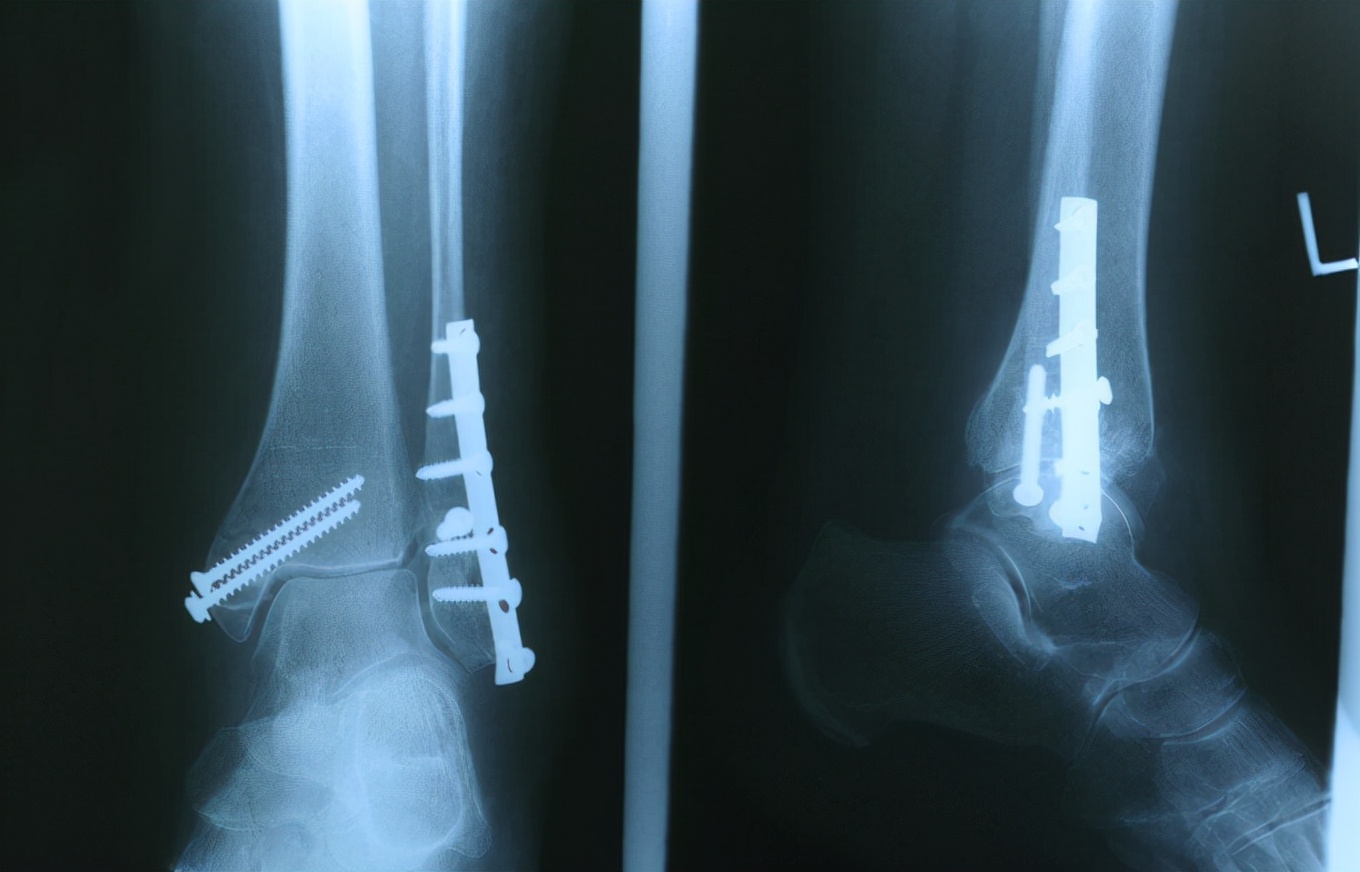

没想到经过检查 , 老张被确诊患上了严重的骨质疏松症 , 骨密度为-2.5 , 骨骼非常的脆弱 , 医生表示 , 稍有不注意就可能会发生骨折 。

5、骨结构异常 , 不能抵抗冲击力 , 摔倒、碰撞后出现骨折;